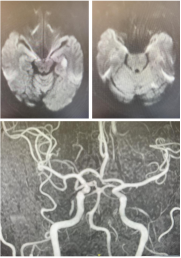

患者因持续头晕四天且症状加重前来泰达医院就诊。经头部核磁检查,提示患者双侧小脑半球及左颞枕叶急性脑梗死,右侧椎动脉颅内段未显影。按照常规诊疗路径,由于其发病已超过急诊手术的常规时间窗,通常会择期进行进一步检查。

团队当机立断,决定打破常规,立即为患者进行紧急脑血管造影。结果证实了超声的判断:左侧椎动脉起始部重度狭窄,伴活动性血栓,随时有血栓脱落风险;右侧椎动脉纤细,未给颅内供血。患者大脑后循环(负责小脑、脑干等核心区域供血)的“生命线”命悬一线。